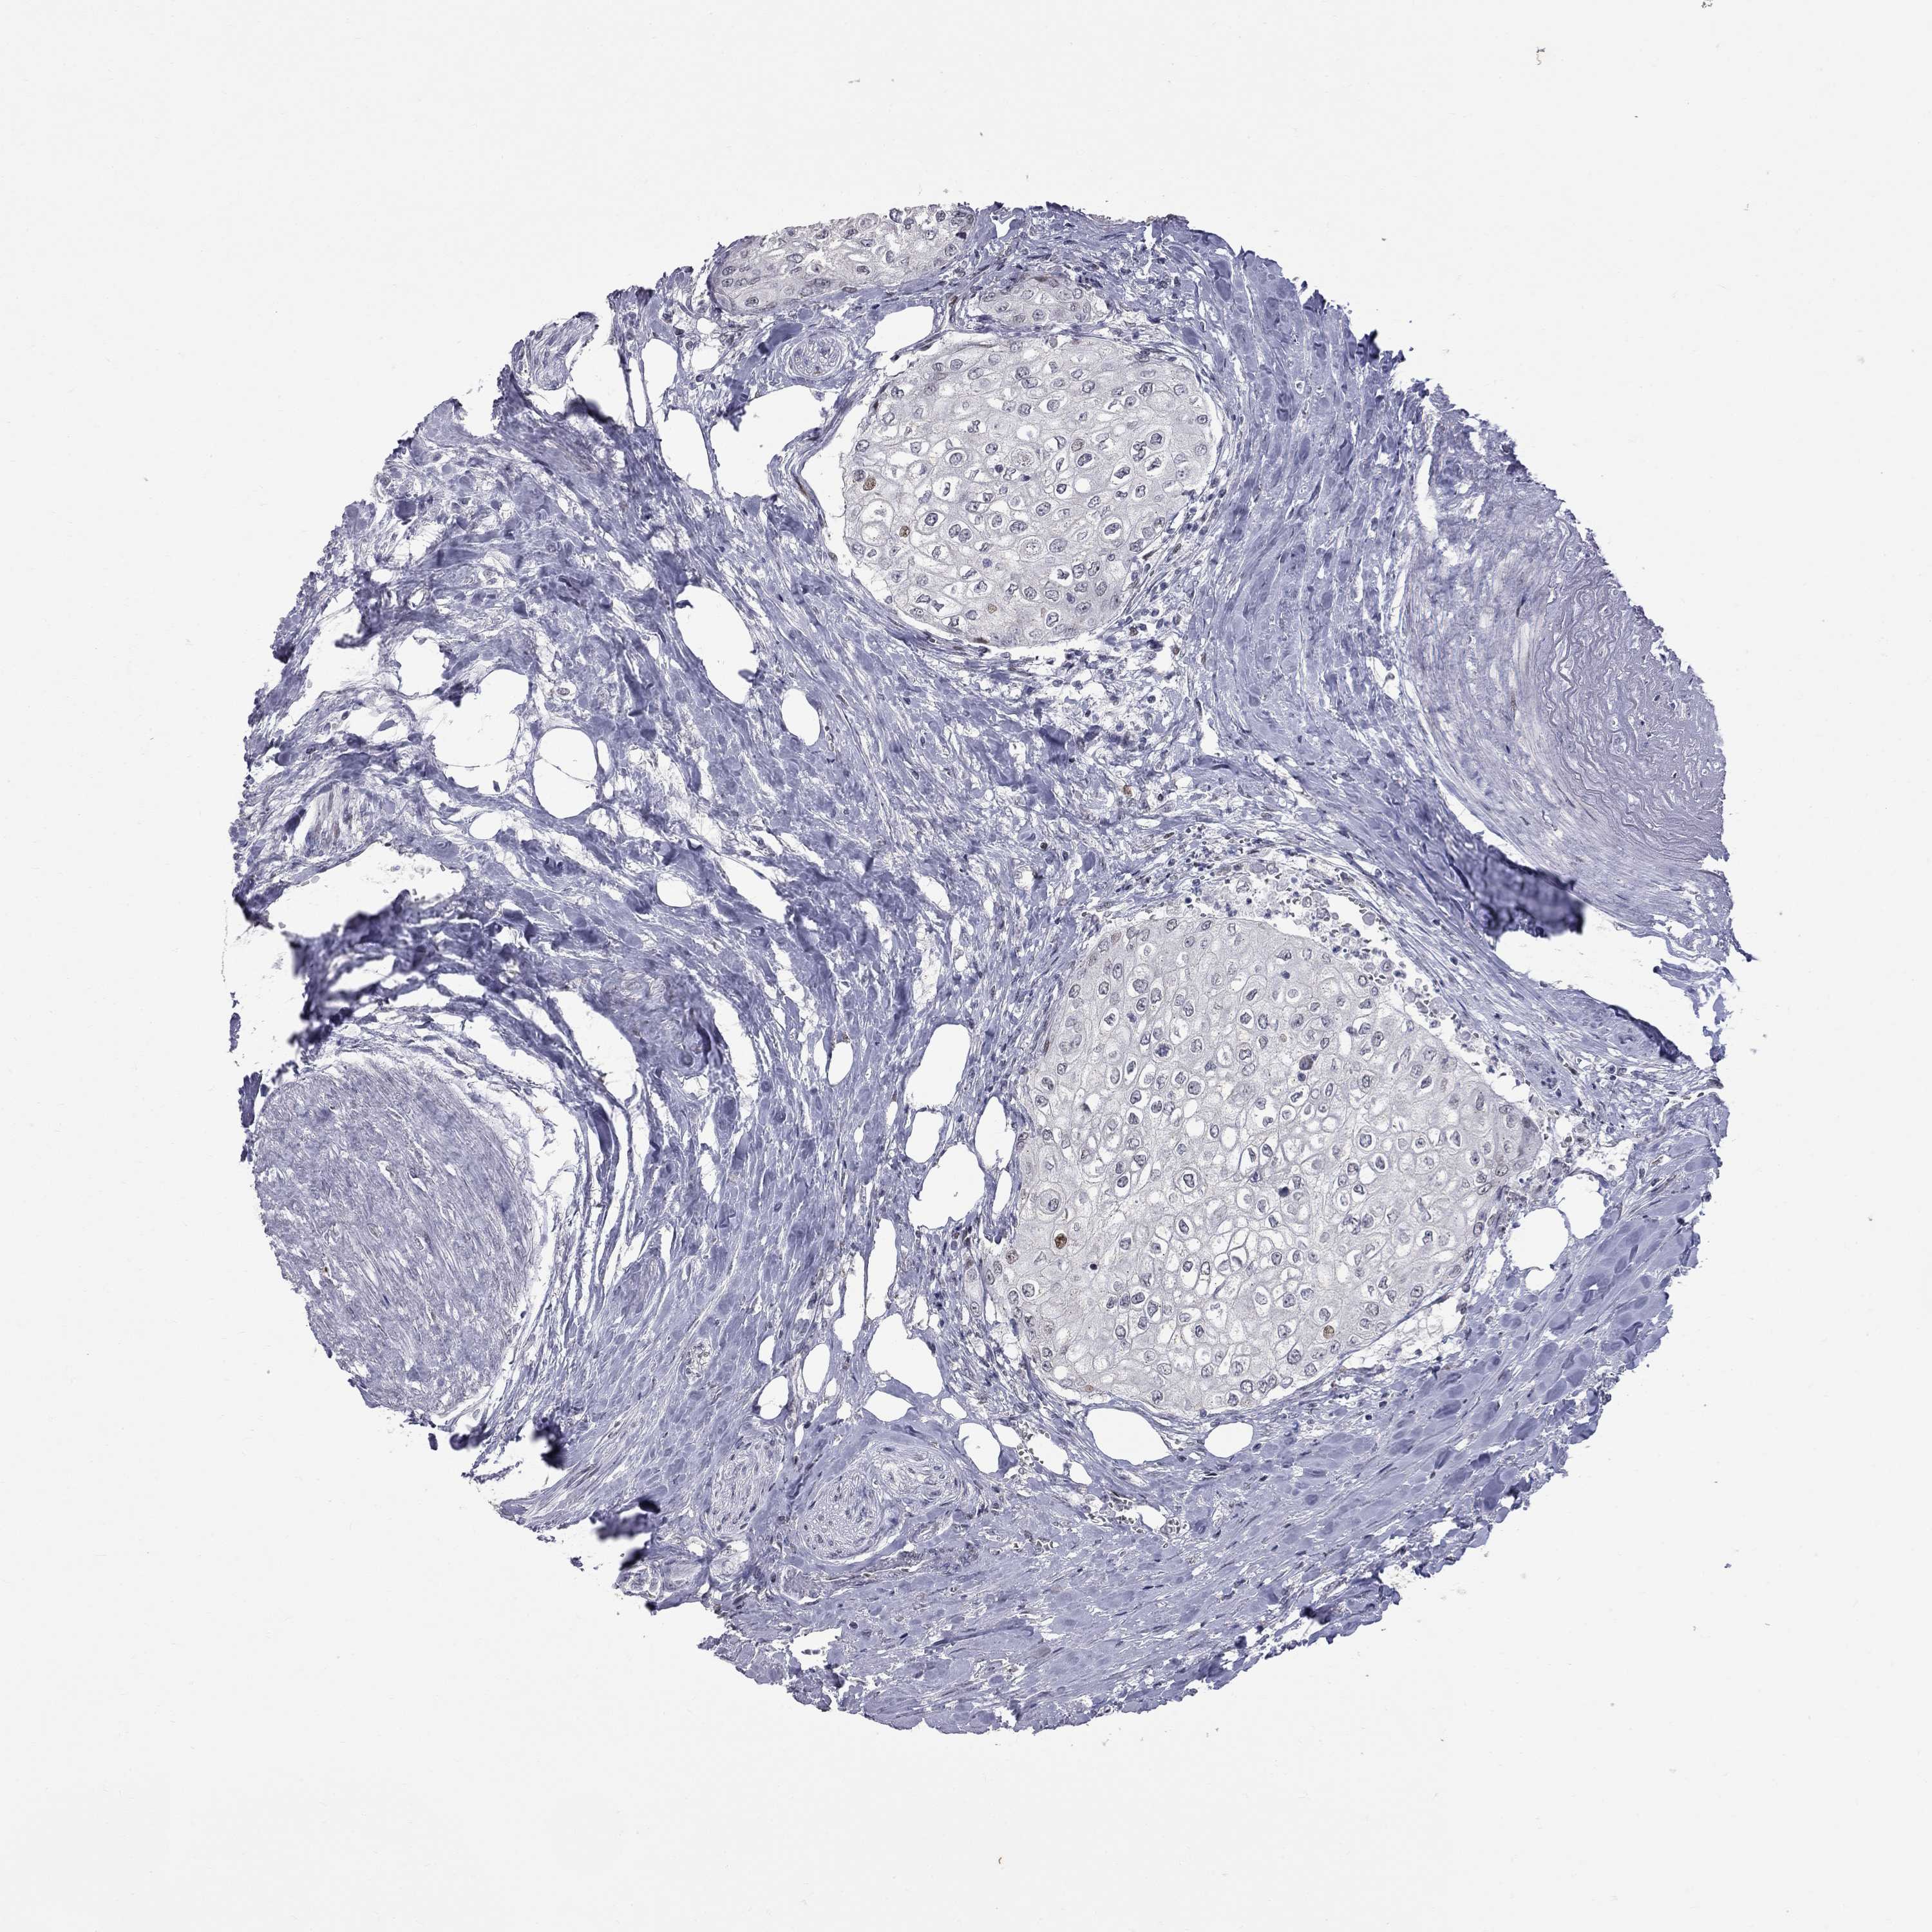

UROTHELIAL CANCER - Protein expressioni

A mouse-over function shows sample information and annotation data. Click on an image to view it in a full screen mode. Samples can be filtered based on level of antibody staining by selecting one or several of the following categories: high, medium, low and not detected. The assay and annotation is described here.

Antibody stainingi

Antibody staining in the annotated cell types in the current human tissue is reported as not detected, low, medium, or high, based on conventional immunohistochemistry profiling in selected tissues. This score is based on the combination of the staining intensity and fraction of stained cells.

Each image is clickable and will lead to virtual microscopy that enables deeper exploration of all samples and also displays staining intensity scores, fraction scores and subcellular localization as well as patient and tissue information for each sample.

Antibody HPA076284

Staining

High

Medium

Low

Not detected

Intensity

Strong

Moderate

Weak

Negative

Quantity

>75%

75%-25%

<25%

None

Location

Nuclear

Cytoplasmic/membranous

Cytoplasmic/membranous,nuclear

Urothelial carcinoma, High grade

Urothelial carcinoma, Low grade